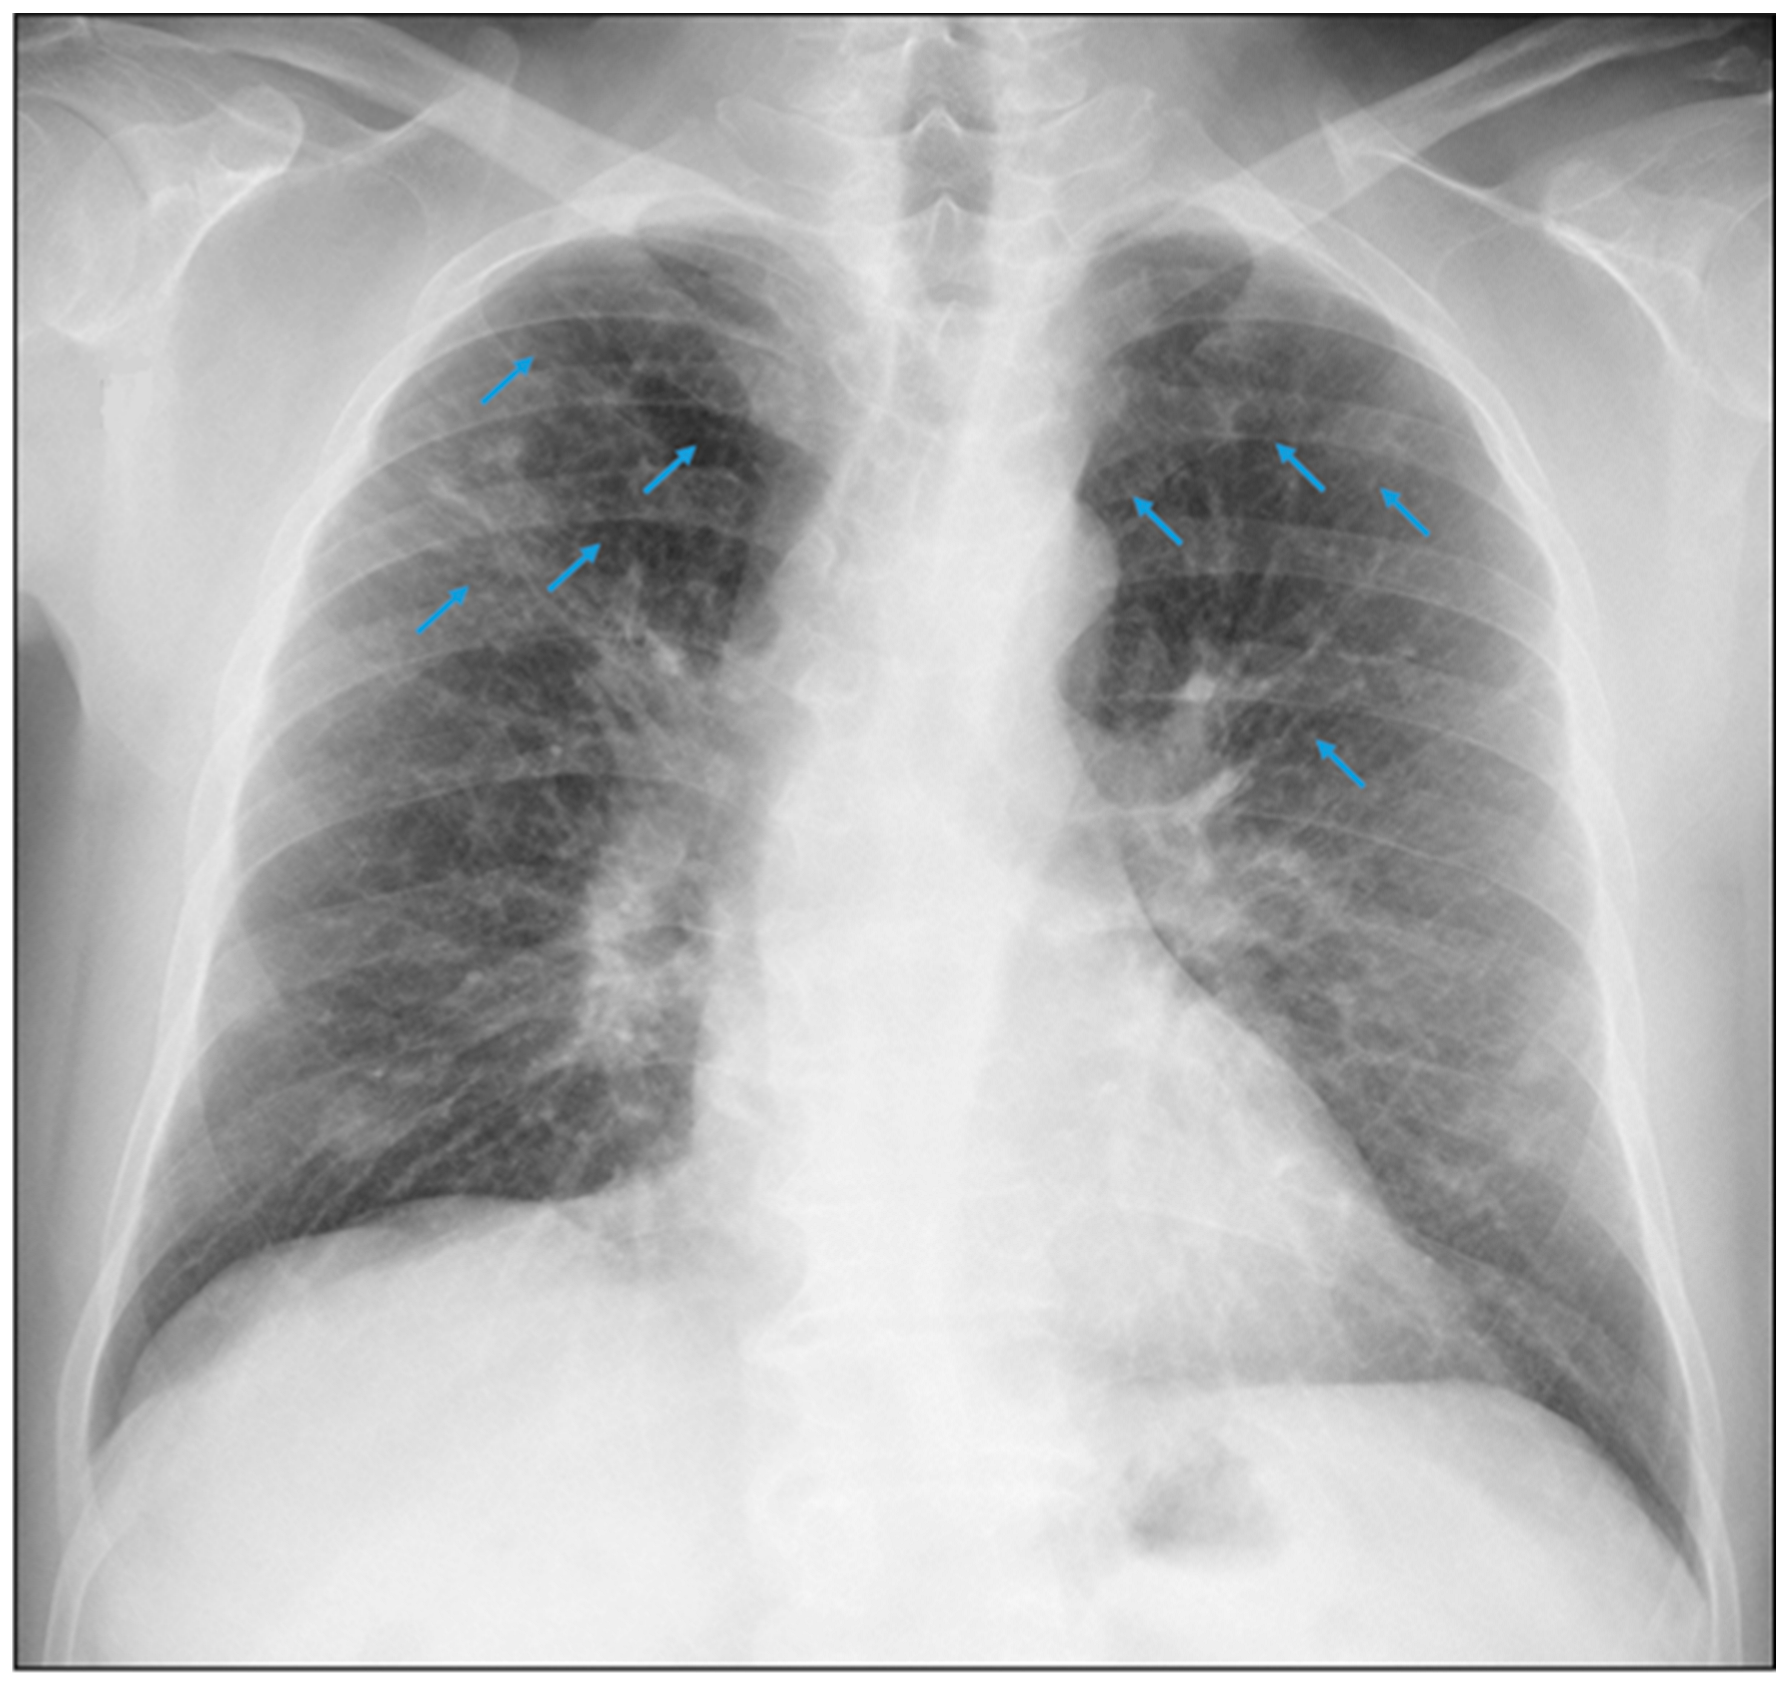

3.1.2. Case 2